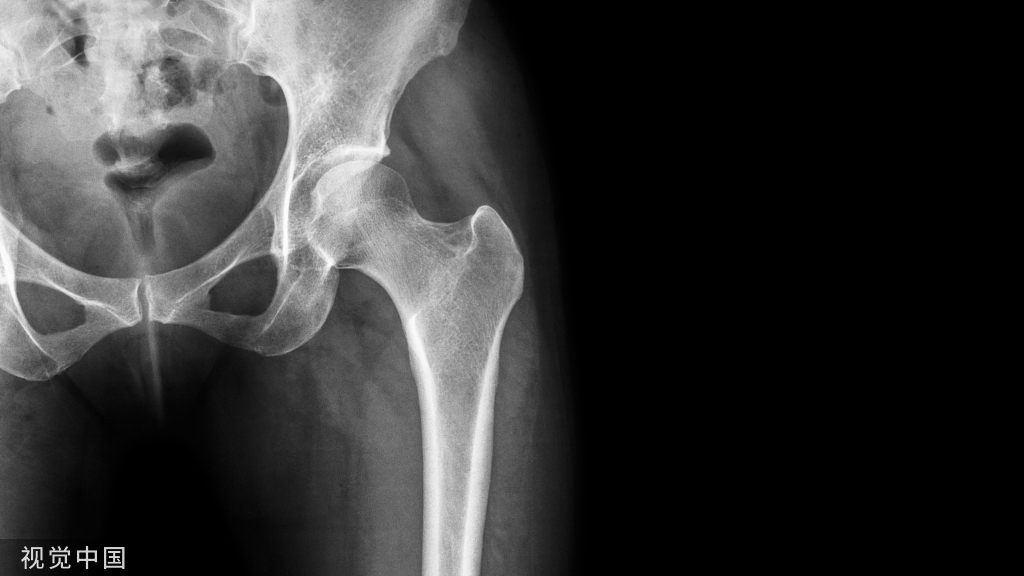

骨盆骨折骶髂螺钉相关知识

(一)请介绍一下骶髂螺钉相关的解剖学知识。